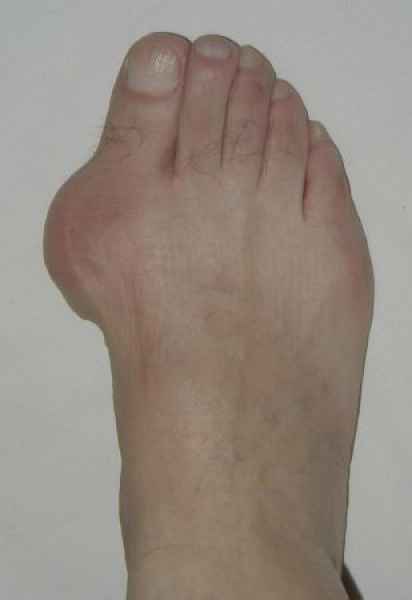

La marcha no solo es característica de la especie humana sino también de cada persona, y más aún varía según el estado de ánimo del momento. Una patología en los pies, se traduce en el rostro, en el ánimo, en el psiquismo. No sólo el dolor produce estos efectos, también un pie deformado o poco estético. En nuestra sociedad, la estética constituye un valor muy apreciado y estas alteraciones causan vergüenza fundamentalmente en las mujeres, que esconden en la playa sus pies en la arena y no pueden usar calzados elegantes.

Tanto la estructura del pie como su funcionalismo que es la marcha, pueden ser asiento y manifestación respectivamente de alteraciones locales ó sistémicas, por lo que su cuidadoso examen resulta de extrema utilidad diagnóstica.